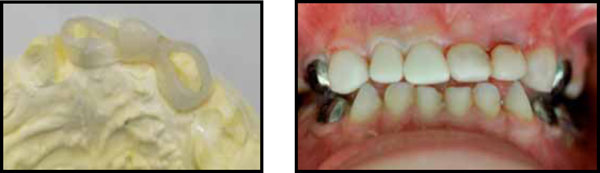

Fig. (10).

The bridge frame and the restored teeth on the mold.

Fig. (11).

MI with the glass-fibers based bridge, before and after bonding with G-aenial Bond.

The glass-fibers bridge on the mold and in the mouth after bonding. Note the class I occlusion reconstructed. Teeth #51-53 were restored using composite coverage.

Fig. (14).

MI, a 3Y6M old boy was treated under general anesthesia due to severe ECC (Early Childhood Caries) and lack of cooperation. The upper primary centrals were extracted and an impression was taken. On the mold a restorative bridge was fabricated using the Perio glass-fibers ribbon (ever-Stick, GC Co, Japan) as base, treated using the Stick-Resin (GC Co Tokio, Japan, lot 1203211) and the missing teeth were restored using A1 G-aenial flowable composite (G-aenial flo, GC Co, Tokyo, Japan lot 1102091) and A1 restorative composite material (Fig. 10). Two weeks after the extractions the bridge was re-treated with Stick-Resin and bonded to teeth #52,62 after 60 seconds etching, rinsing for 10 seconds and drying, using the G-eanial bond according to manufacturer instructions and light cured for 60 seconds (Fig. 11). The glass fibers base on teeth #52,62 was coated with flowable composite.

IM, a 4 years old boy was treated under GA due to severe ECC (Fig. 12). An impression was taken prior to treatment and a glass-fibers based bridge was fabricated. During the treatment, tooth #62 was extracted and the fabricated bridge was bonded similar to the previous case to teeth #61,63 (Fig. 13). Teeth #51,52,53 were restored using the pediatric strip crown forms (3M/ESPE) and A1 restorative composite material after 60 seconds etching and bonding with G-aenial bond (GC Company, Japan).